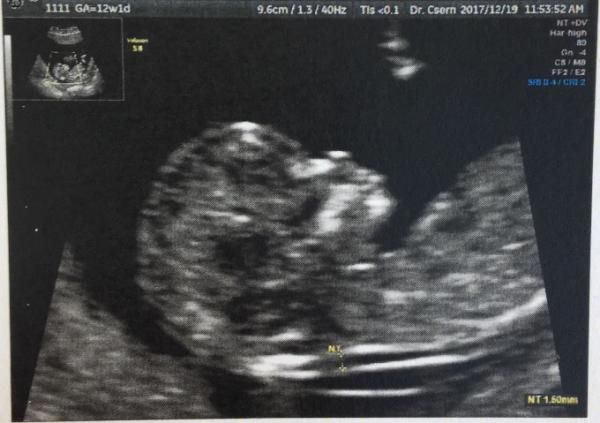

Ahhhh.... Ich bin soooooooo erleichtert!!!! Alles supi!!!!! NT ist 1.5 mm, Herzchen gut entwickelt. Nach 2 FG will ich endlich ein SS geniessen Und eine Tendenz zu Team Blau gab auch Ich bin endlich bereit für Weihnachten!!! Ich hab schon mein Geschenk bekommen! Lg, Alida

Bild zu FA Termin- Nackenfaltenmessung - Forum für Juli - Mamis